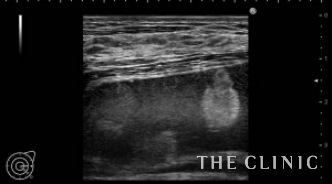

2年前に他院で脂肪注入による豊胸を受けられた方です。

これまで多くの脂肪による豊胸後のしこりを治療してきましたが、大胸筋下のしこりはほとんどありませんでした(シリコンバッグ抜去後のカプセル内のしこりはあります)。大胸筋下は、血流の関係か、スペースが少ないためか、大きなしこりになることはほとんどありませんが、この方は、大胸筋下に注入した脂肪が9㎝大のしこりになっていました。